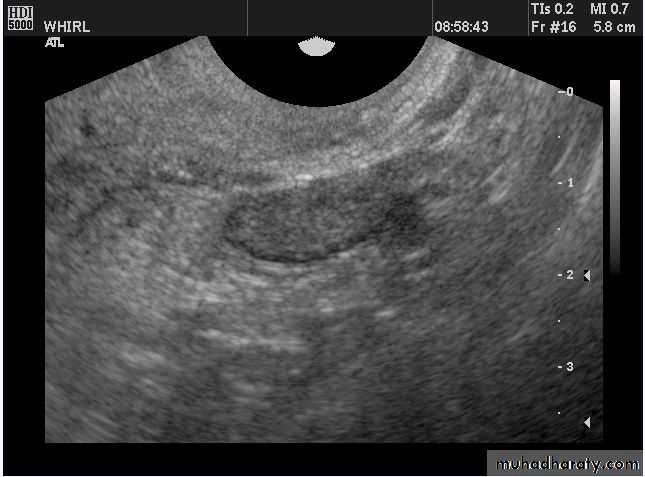

Ovarian hyperstimulation syndrome (OHSS):

• Ovarian hyperstimulation syndrome (OHSS):

Transvaginal ultrasound images of ovarian hyperstimulation syndrome:

This young adult female patient showed multiple large theca lutein cysts of both ovaries, arranged in spoke-wheel pattern (ultrasound images above) which were the result of use of gonadotropins in the management of infertility. The cysts vary in size from 2 to 4 cms. with the ovaries massively enlarged (each ovary measures up to 7 cms. in size). This can be classified as grade-2 hyperstimulation of the ovaries (ovarian diameter from 5 to 10 cms.). There is not evidence of ascites. The color Doppler image of the ovaries shows vessels passing along the margins of the cysts. One of the complications of such enlarged ovaries in OHSS is torsion and in certain cases rupture of the ovaries, both of which are medical emergencies. Ovarian hyperstimulation syndrome is known to occur more frequently in patients of pre-existing Polycystic ovaries (PCO).